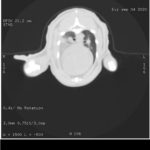

Gracias a vosotros por fin hemos podido realizar el TAC que necesitaba Allan. Os dejamos por aquí algunas de las imágenes y el primer informe emitido por el hospital.

Allan sigue ingresado y tendrá que estarlo varios días más, no sabemos aún cuántos. Deben estabilizarlo y observarlo antes de valorar si es conveniente operarlo. El estado del tórax sigue siendo delicado y tienen que controlar el encharcamiento que tiene en un pulmón. El TAC ha mostrado, además de nuevas fracturas, fracturas anteriores. Es decir, Allan no sólo está así porque recientemente haya recibido un golpe, sino que tiene signos de haber recibido al menos otro golpe anteriormente que también le produjo fracturas, unas fracturas que “se han soldado como han podido”. Como no tenemos ninguna información de Allan hasta la pasada semana que fue cuando recibimos el aviso, no sabemos si antes era capaz de caminar o de hacer caca él solito.